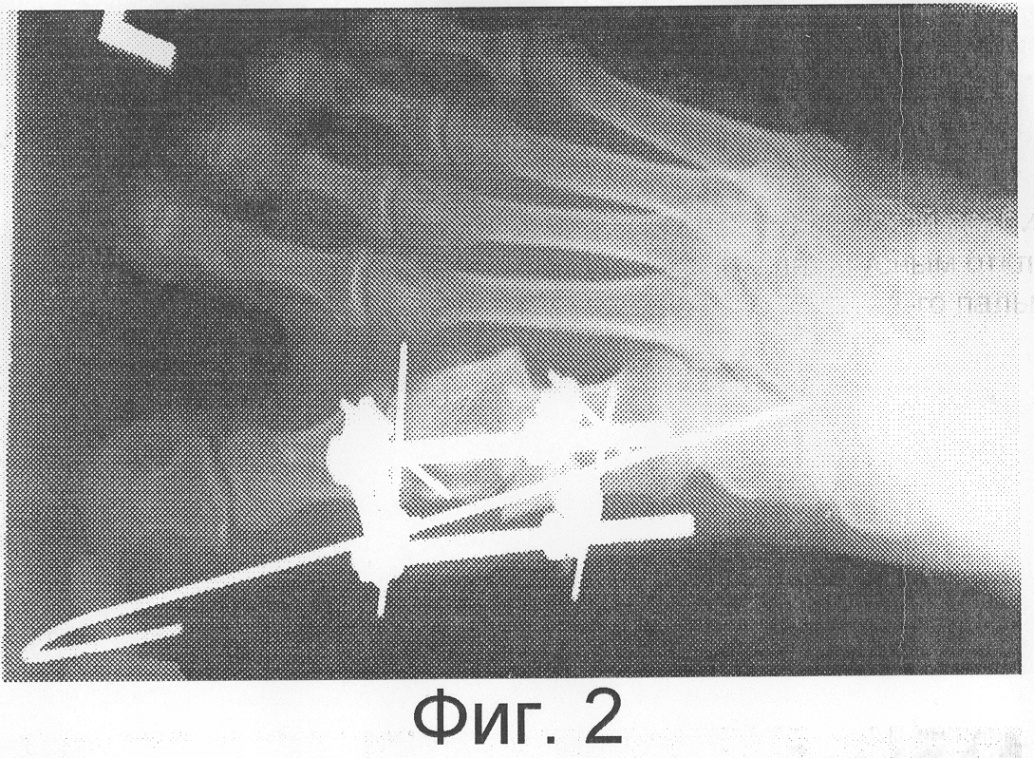

Аппарат демонтирован через 4 недели. Деформация устранена, правильная ось сустава восстановлена, болевой синдром не определяется. На Фиг.4 представлена рентгенограмма правой стопы в прямой проекции после лечения.